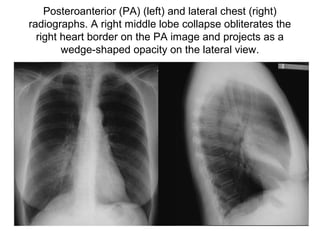

Posteroanterior (PA) (left) and lateral chest (right)

radiographs. A right middle lobe collapse obliterates the

right heart border on the PA image and projects as a

wedge-shaped opacity on the lateral view.